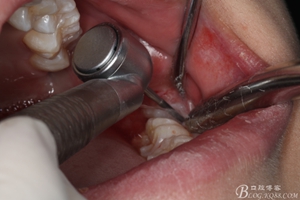

圖11.去骨---暴露出38的牙冠最大周徑

圖12.高速牙鉆分牙